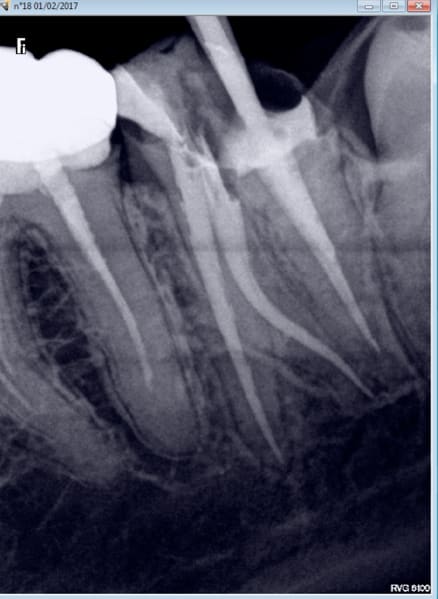

02/02/2017 à 13h20

tu me montres 2 radios en incidence oblique de 2e MV obturés et je m'achète un lab )))

Et d'une. RTE s'il vous plait. -)